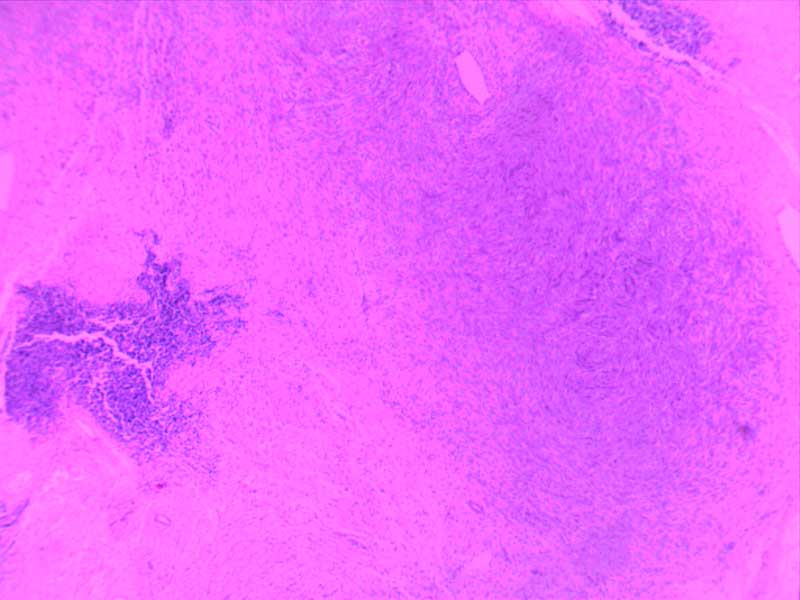

绒毛膜癌-10倍

肉芽组织-10倍

乳头状瘤(膀胱)4倍

乳腺癌-4倍

乳腺癌-10倍

神经鞘瘤4倍

神经鞘瘤-10倍-(2)

神经鞘瘤-10倍

大叶性肺炎(红肝期)10倍

大叶性肺炎(红肝期)-10倍

大叶性肺炎(灰肝期)-4倍

大叶性肺炎(灰肝期)-10倍